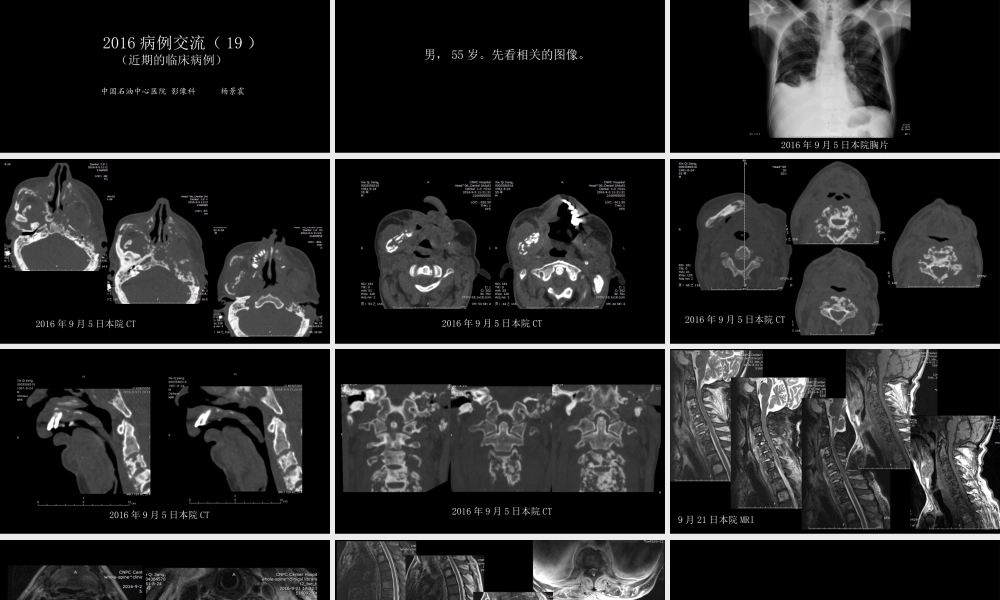

没有见过的弥漫性骨质破坏:?2016病例交流(19)(近期的临床病例)中国石油中心医院影像科杨景震男,55岁。先看相关的图像。2016年9月5日本院胸片2016年9月5日本院CT2016年9月5日本院CT2016年9月5日本院CT2016年9月5日本院CT2016年9月5日本院CT9月21日本院MRI9月21日本院MRI9月21日本院MRI接下来?问病史:近两年一直断续发热,为低热、有时体温达39°C,颌面部肿胀,无破溃。再复习一下以往外院的胸片及颌面部的CT2013年10月CT当时的胸片肺、肋骨均未见异常2013年10月CT2013年12月外院CT2013年10月因牙源性感染在北京301医院手术刮除,术后诊断左侧下颌骨骨髓炎。同年12月在另家医院行第二次手术治疗,诊断左侧下颌骨骨髓炎。之后,未曾就医,2016年9月5日来本院复查,即前面的头颈部的CT及胸片、脊柱MRI(呼吸科证实菌血症)。简单回顾:本例结合既往的病史以及治疗过程,影像学的骨改变依然诊断慢性骨髓炎,病变反复发作及扩展,除左侧颅面骨外,还累及右侧颜面骨、颅底骨、多肋骨、胸骨以及颈椎、胸椎多椎体及附件。椎体的病变之广泛,却没有压缩表现,推测是骨破坏的同时存在较多的成骨,也符合慢性硬化性骨髓炎特点。鉴别:结核病、骨肿瘤等。END